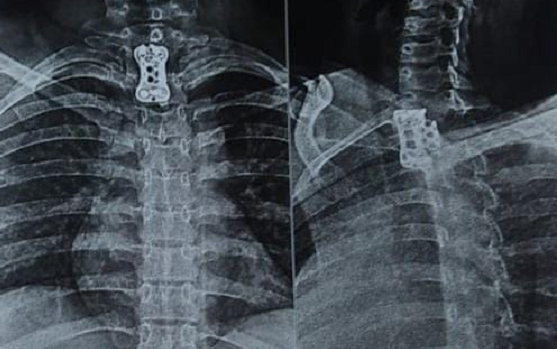

Dr. Somashekar D is an experienced spine surgeon in Bangalore. He is currently practising as a Consultant - Spine Surgery at Manipal Hospital Jayanagar, Bangalore. With nearly 10+ years of expertise in spine care, Dr. Somashekar has established himself as a highly skilled spine surgeon, contributing to over 1,500+ spine surgeries independently, ranging from simple decompressions to complex spinal reconstructions. His practice is deeply rooted in precision-based techniques and evidence-guided clinical protocols, ensuring both safety and long-term functional outcomes for his patients. He is a top spine surgeon in Jayanagar.

We offer comprehensive treatment for spine issues that is on par with any leading spine center worldwide. Our services encompass both non-surgical and surgical treatments tailored to address your specific condition. Our expertise covers a wide range of spine surgeries, including minimally invasive spine surgery, cervical spine surgery, scoliosis surgery, and complex spine surgeries.

Covers a wide range of spine surgeries, including complex spine surgeries.